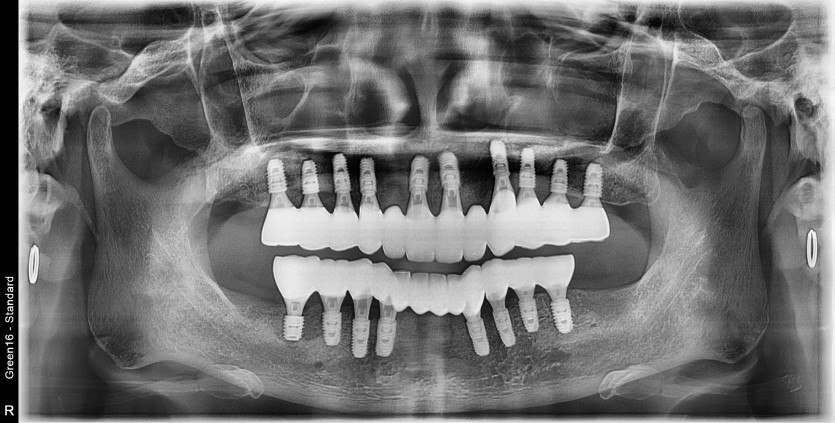

전체 임플란트 증례입니다.

18개의 임플란트로 완성하였습니다.